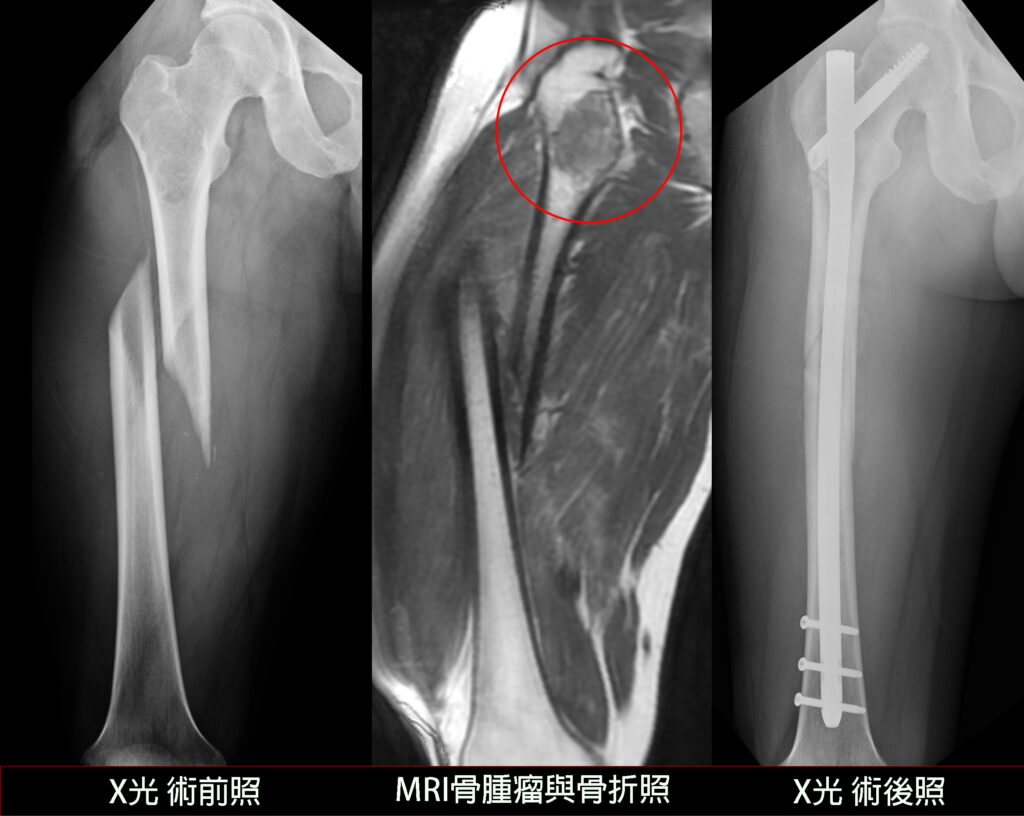

術前術後對照圖。(記者孫義方攝)

〔記者孫義方台中報導〕台中市三十歲的李先生去年底在日本滑雪,從滑雪纜車下車時不慎摔倒,大腿變形,檢查後發現大腿骨中段骨折竟合併近端六公分骨腫瘤。由於腫瘤性質不明且日本當地醫院無骨腫瘤治療團隊,只能先打上外固定鋼架返台就醫。所幸腫瘤為良性,醫師將腫瘤組織徹底刮除,復位大腿骨折,並植入骨髓內鋼釘同時穩固骨腫瘤刮除後的空洞與骨折部位,順利康復。

楊鎮源部長指出,此案困難點在於,患者面臨嚴重骨折與性質不明的骨腫瘤,治療策略必須兼顧「確認骨腫瘤的良惡性」、「徹底清除骨腫瘤」與「骨折復位固定」。為了確保手術安全,他在術前會診放射科與病理科後制定計畫,並在手術一開始便針對骨腫瘤組織進行冰凍切片化驗。

所幸初步化驗結果證實腫瘤為良性,他隨即將腫瘤組織徹底刮除,復位大腿骨折,並植入骨髓內鋼釘同時穩固骨腫瘤刮除後的空洞與骨折部位,透過跨科整合,一次性解決了原本複雜的雙重難題。一周後正式的病理報告證實是良性的纖維發育不全(Fibrous dysplasia),患者與家屬也終於可以放下心中的擔憂。